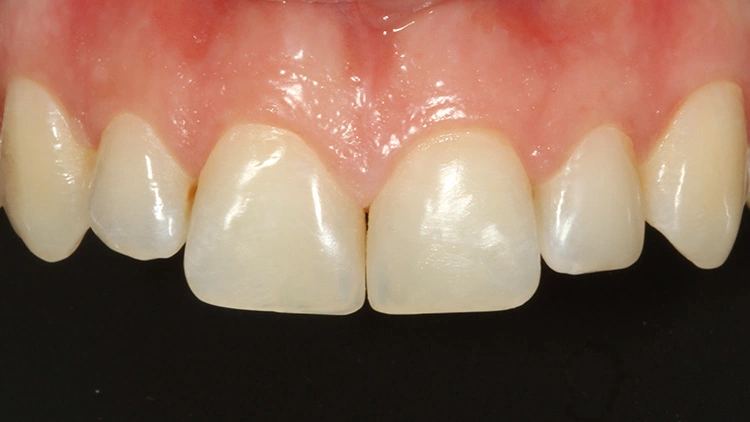

Die Abbildung 42 zeigt den komplett fertiggestellten Zahn 21 mit der nach mesial extendierten Verbreiterung und der Ausbesserung des inzisalen Schneidekantendefektes, in der Abbildung 43 ist der entsprechend versorgte Zahn 22 zu sehen. Aufgrund der kleinvolumigen Anbauten kam bei den 3 Zähnen ausschließlich die Tetric Prime Universalfarbe A2 zur Anwendung; die A2-Dentin-Masse war diesmal nicht erforderlich. Prof. Dr. Ernst

Auch dieser Fall verdeutlicht die einfache Anwendungstechnik mit einer doch sehr reduzierten Materialpalette, die dennoch ein gut vorhersehbares und ästhetisch ansprechendes Versorgungsergebnis erzielen kann (Abb. 44). Hier ist weniger oftmals mehr. Dass sehr häufig mit Monofarben durchaus sehr schöne Ergebnisse zu erzielen sind, zeigen diverse andere Fallberichte zu diesem Thema [12,15–18]. Prof. Dr. Ernst